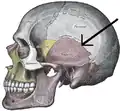

The squamosal suture, or squamous suture, arches backward from the pterion and connects the temporal squama with the lower border of the parietal bone: this suture is continuous behind with the short, nearly horizontal parietomastoid suture, which unites the mastoid process of the temporal with the region of the mastoid angle of the parietal bone. The term parietotemporal suture may refer to both of these sutures or exclusively to the parietomastoid suture and its use is, therefore, best avoided.

- Side view of the skull. Squamosal suture indicated by the black arrows.